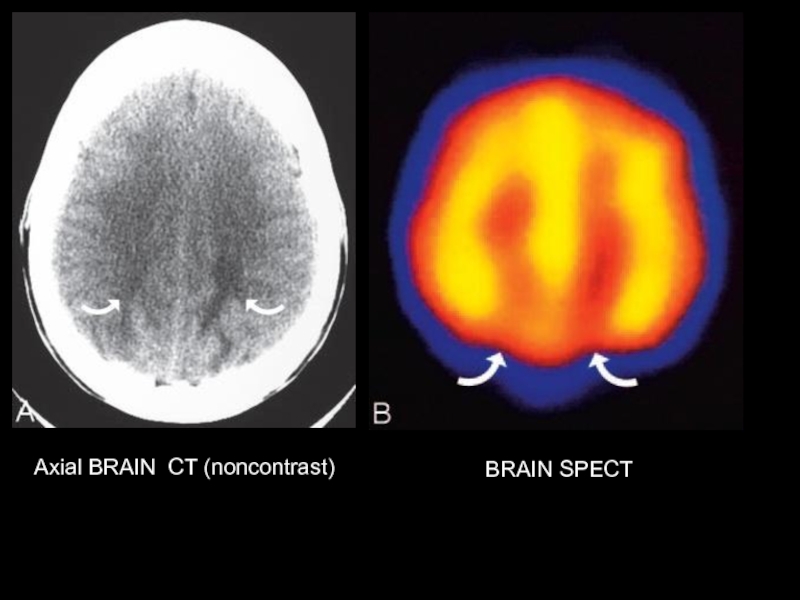

Axial BRAIN CT (noncontrast)

BRAIN SPECT